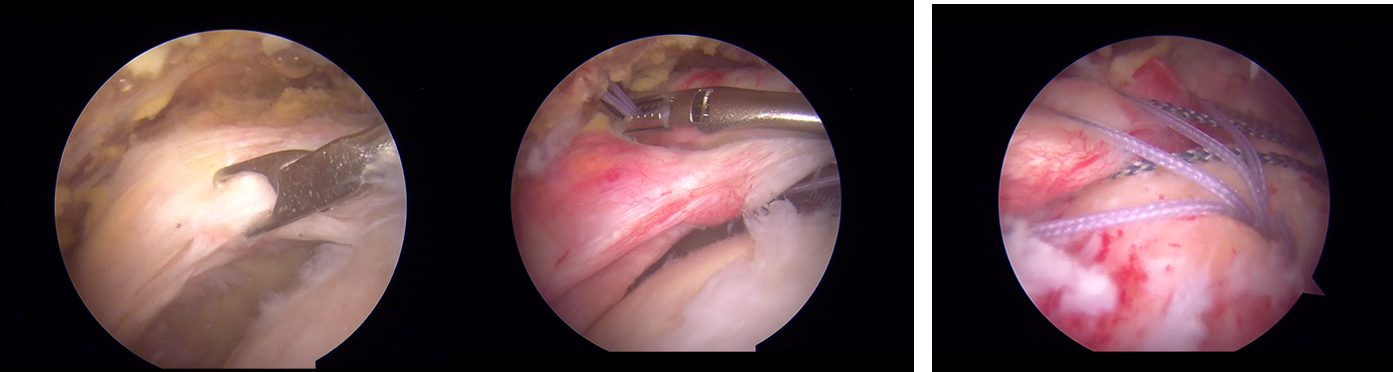

鏡視下腱板修復術 肩腱板断裂に対する手術 Ar Ex 尾山台整形外科

洗濯物を干す動作が困難となった棘上筋不全断裂症例の 理学療法を経験した。腱板断裂は断裂形態から部分断裂 と完全断裂に大別され、一般的に断裂した腱板の自然治 癒は期待されないが、保存療法(理学療法)により症状 が改善するという報告も多い2)。本症例においては部分筋の中でも棘上筋は腱板断裂や肩峰下インピン ジメント症候群において最も障害されやすい筋 であるため,棘上筋の機能評価は重要である3). 棘上筋の機能を評価する方法として,full can test とempty can testがある.先行研究において,年にCodman5)が棘上筋断裂の手術例を報告して以来、 棘上筋筋腹を周囲より剥離して前進させる方法6)や、 冷凍乾燥させた腱を移植する方法7)が報告され、 McLauphlign法に代表される直視下修復